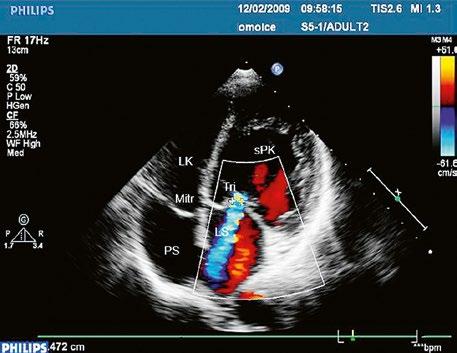

Poslechový nález systolického šelestu nad plicnicí s fixním rozštěpem 2. ozvy je nenápadný. Echokardiograficky je patrná dilatovaná a objemově přetížená pravá komora s paradoxním pohybem septa (Obr. 45.9), zkratový tok může být vidět i transtorakálně (TTE) (Obr. 45.10, Video 45.3, Video 45.7), ale suverénní diagnostickou metodou je jícnová echokardiografie (TEE), případně s 3DE zobrazením (Obr. 45.1, Obr. 45.2,

Obr. 45.10 TTE, čtyřdutinová apikální projekce s levo pravým zkratem na úrovni síní (šipka) při defektu septa síní typu secundum PK – pravá komora, LK – levá komora, LS – levá síň, PS – pravá síň

Poslechový nález kromě fixního rozštěpu 2. ozvy mívá i systolický šelest na hrotu při mitrální insuficienci. Suverénní je echokardiografická diagnostika (Obr. 45.14, Obr. 45.15, Video 45.10, Video 45.11, Video 45.12, Video 45.14), včetně jícnové echokardiografie (TEE) a trojrozměrného zobrazení (3DE), které upřesní nejen velikost síňové složky defektu, ale přítomnost komorové složky defektu či jiných zkratů,

abnormalit mitrální chlopně, nejčastěji „rozštěpu“ předního cípu (Obr. 45.20, Obr. 45.21, Video 45.15, Video 45.16), abnormálních úponů mitrální chlopně, přítomnost subaortální stenózy a jiných abnormalit. Katetrizaci doplňujeme při podezření na plicní hypertenzi, zvláště u kompletních AVSD, při neinvazivním odhadu systolického tlaku v plicnici nad 40 mmHg.(7) Srdeční magnetická rezonanace (CMR) se uplatní při